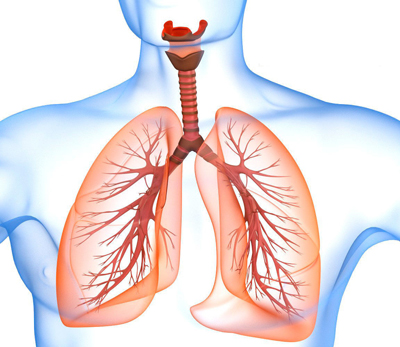

علت، علایم و درمان آب آوردن ریه

به طور معمول بین ریه و قفسه سینه فضایی وجود دارد که به آن فضای جنب گفته می شود. داخل آن نیز همیشه ترشح وجود دارد که جذب خون می شود. زمانی که این مایع افزایش پیدا کند، اصطلاحا گفته می شود آب آوردن ریه. آب آوردن ریه همیشه به دلیل مشکلات ریه نیست. دلایل …

ادامه ی نوشته علت، علایم و درمان آب آوردن ریه